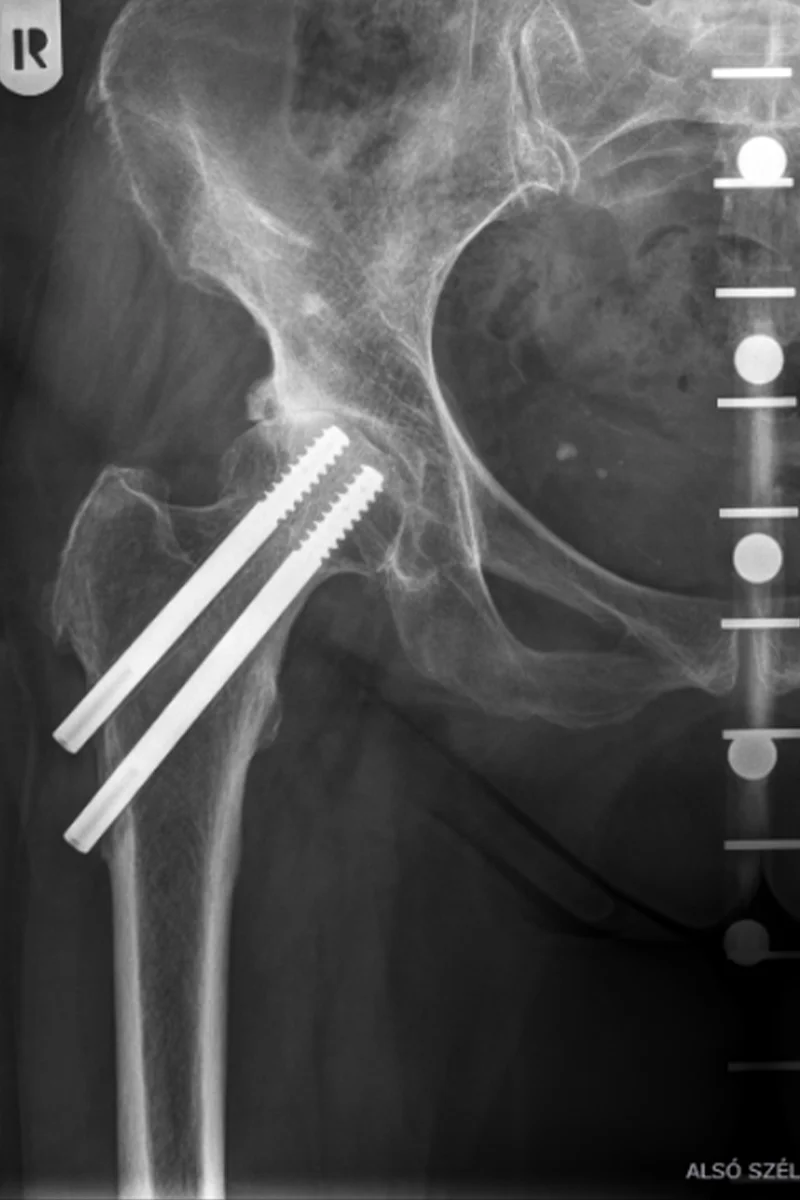

Ez egy pertrochanter törés utáni kép. Kérem keressenek kettős kanülált csavarozás utáni képet. Főleg, ami nem gyógyul.